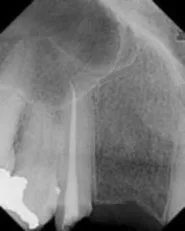

Anterior Implant and Crown

Before

After